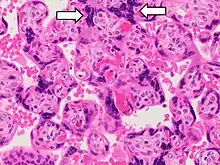

- Increased syncytial knots